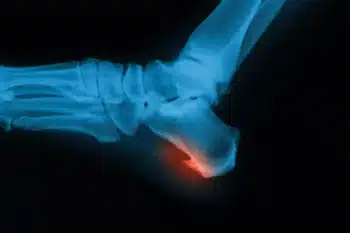

Heel Spurs

Heel spurs are the result of calcium deposits that cause bony protrusions on the underside.

Types of Heel Spurs and Their Causes

Heel spurs are bony growths that can form on the heel bone in response to.